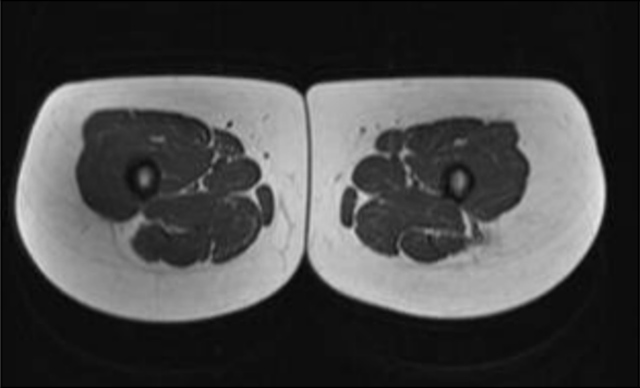

Vergleich des Oberschenkelquerschnitts eines Fettleibigen und Normalgewichtigen